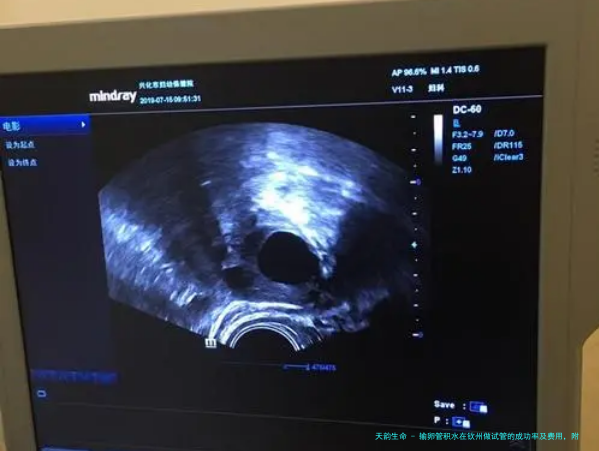

输卵管积水是女性不孕症的常见原因其中之一,会影响精子和卵子的结合,从而导致不育。要是您正处于寻找试管婴儿治疗,哪样认知钦州地区输卵管积水做试管婴儿的成功率和费用是极为重要的。

试管婴儿成功率受多种因素影响,包括年龄、不孕缘故、既往怀孕历史等。一般来说年纪较轻的女性成功率较高。在钦州,输卵管积水灾者试管婴儿成功率均匀约为40%-60%。但请关注,每个人的情况都是特别的,成功率可能因个人差异而略有差异。